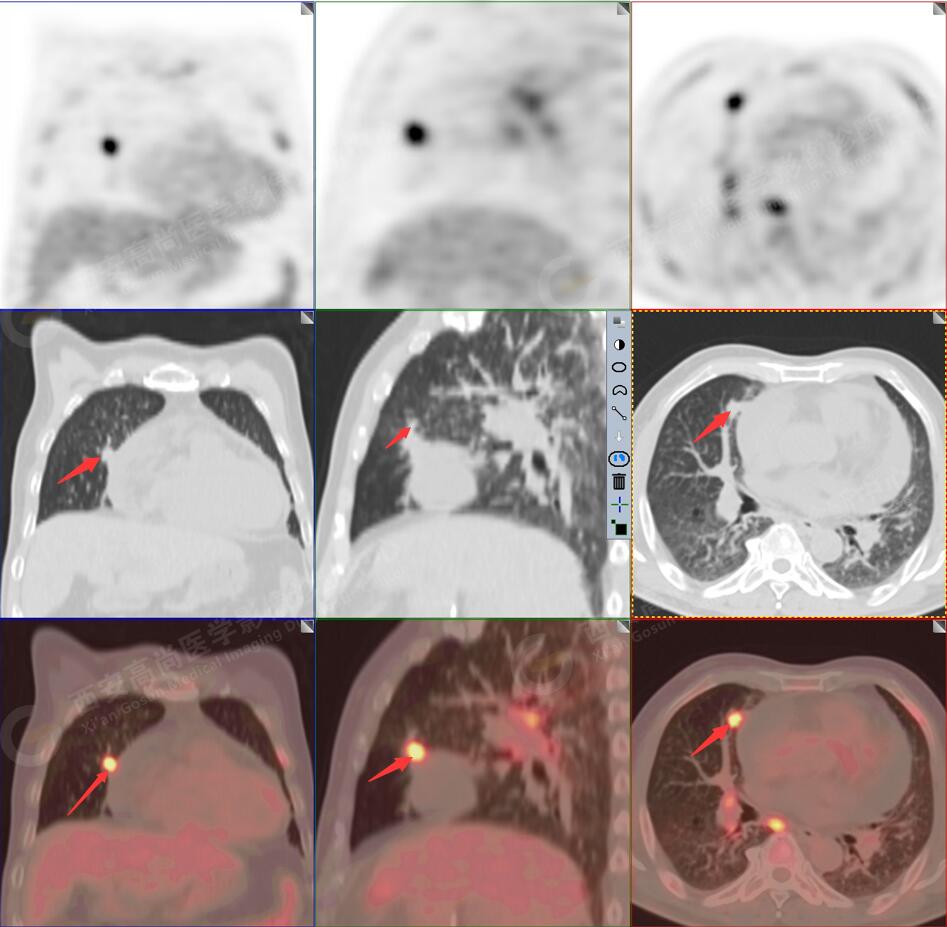

1.以下為肺內(nèi)原發(fā)灶

1.右肺中葉內(nèi)側段軟組織結節(jié),呈淺分葉狀,邊緣可見毛刺及胸膜牽拉征,呈FDG代謝異常增高,考慮為周圍型肺癌。

2.雙肺內(nèi)彌漫性分布大小不等實性小結節(jié)灶及粟粒狀高密度影,均未見FDG代謝明顯異常增高,均多考慮為癌性淋巴結炎及轉移性病變。